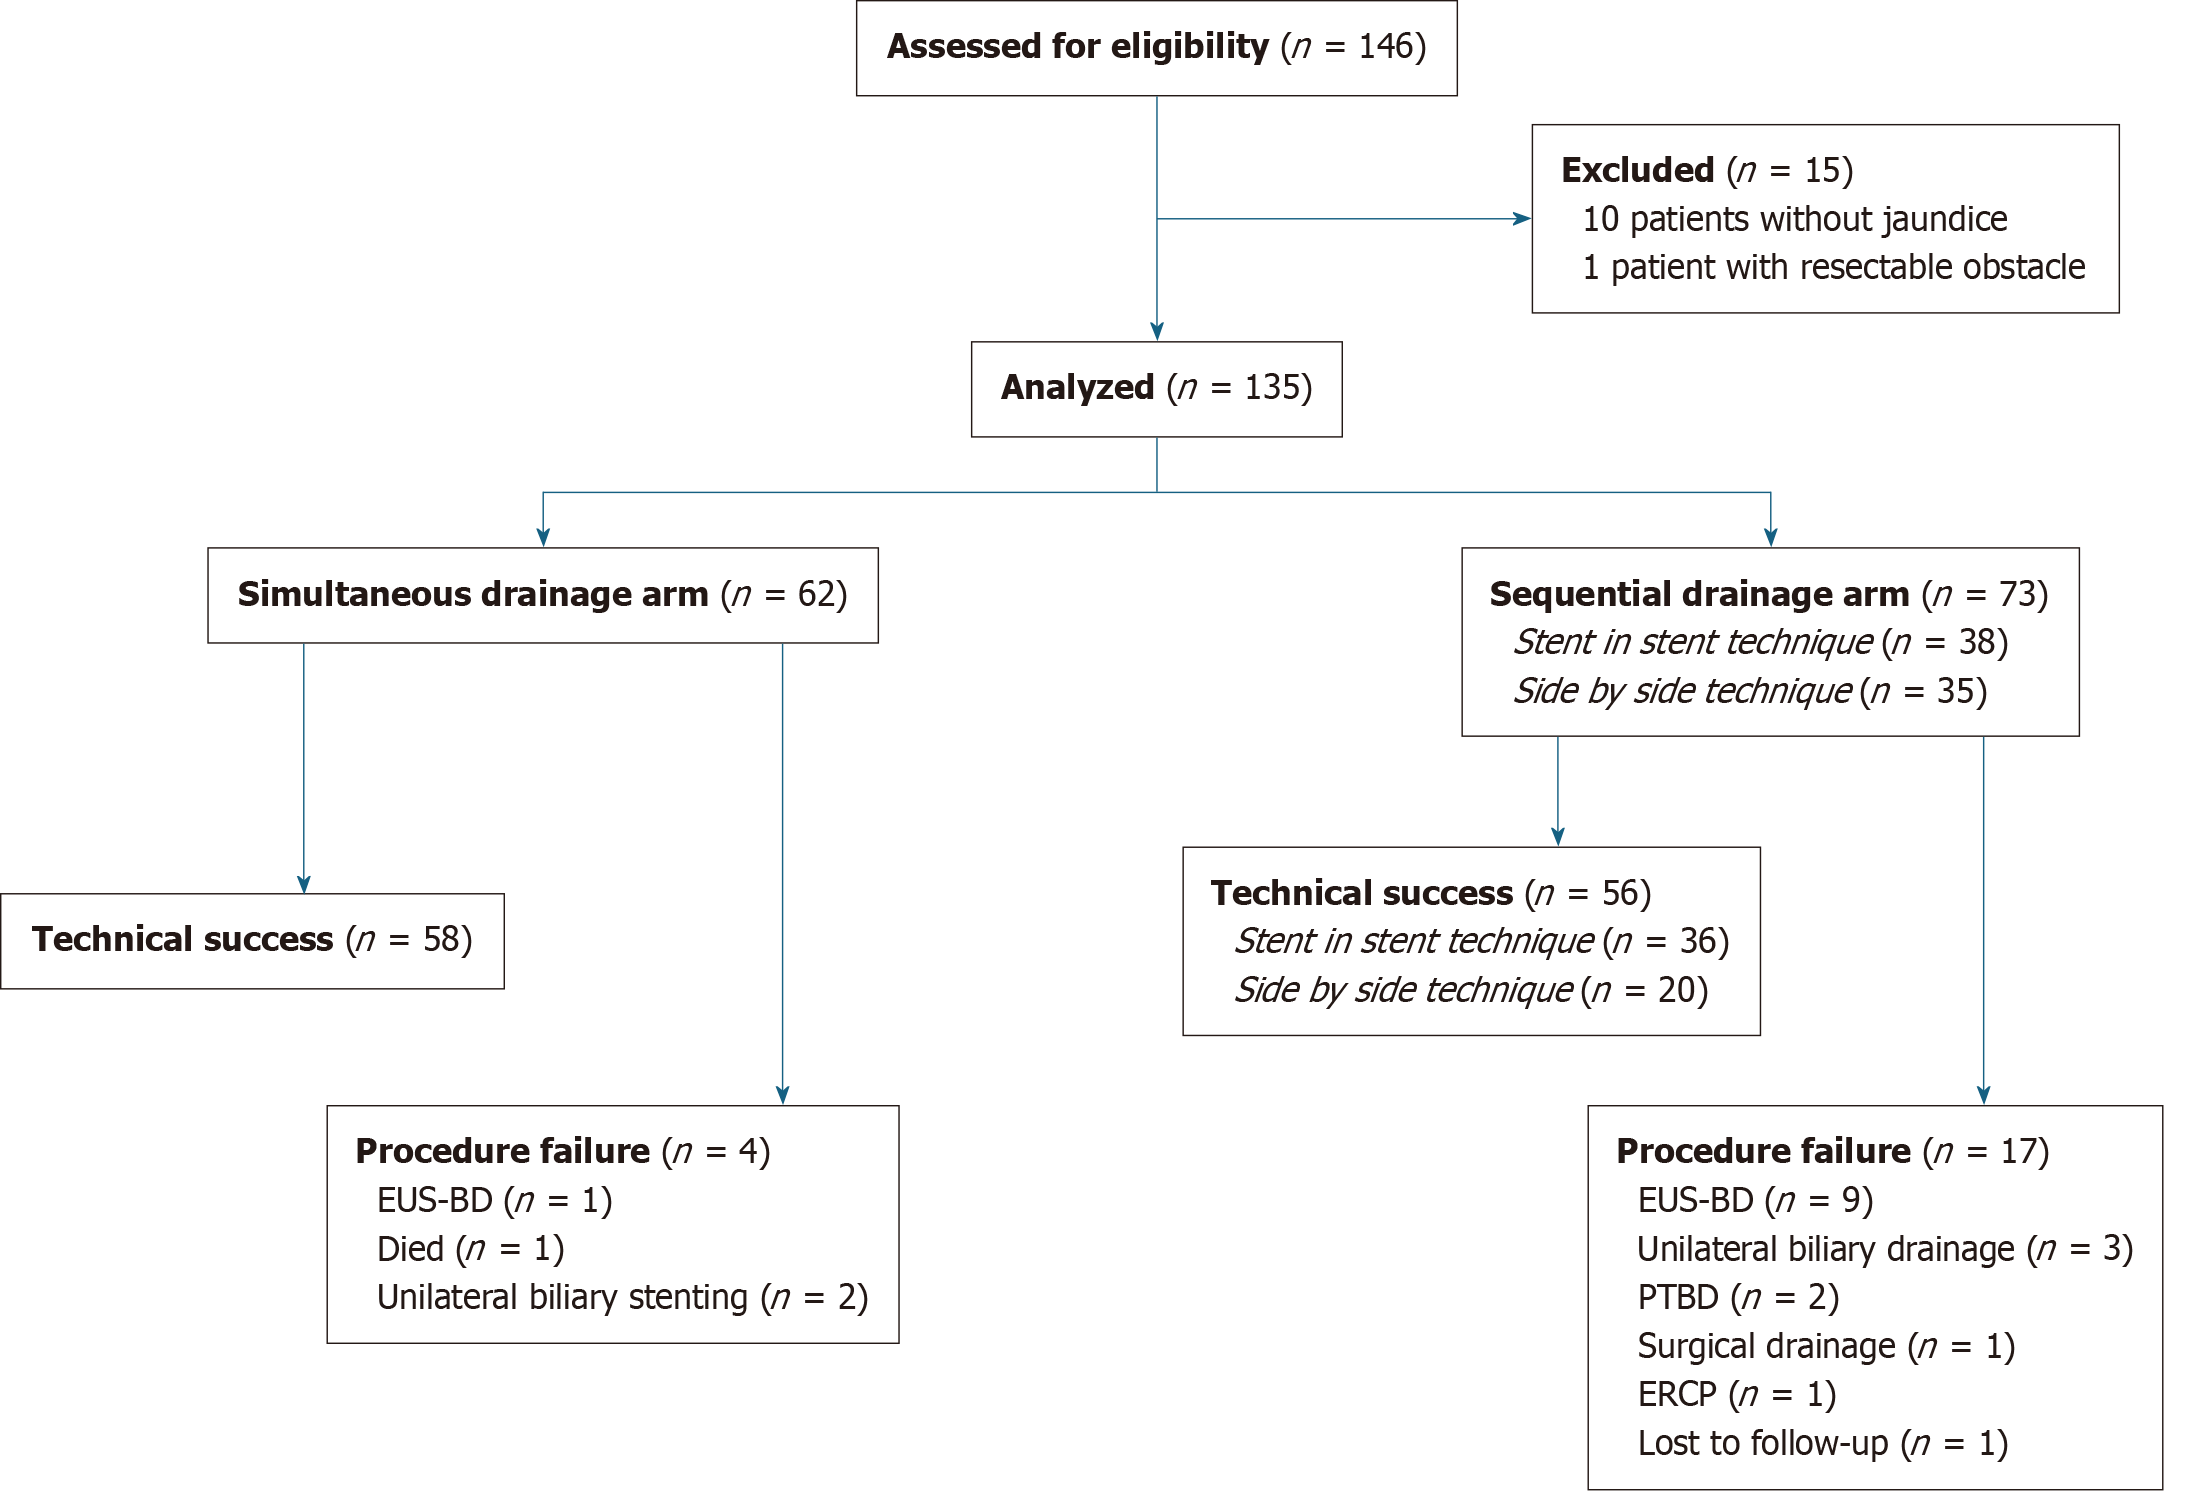

Figure 2 Sequential side by side bilateral drainage on X-ray and endoscopic view.

A: Placement of guidewires across the strictures; B: Dilation of left stricture; C: Dilation of right stricture; D: Simultaneous placement of two metallic biliary stents; E: Endoscopic view after drainage with two biliary self-expandable metallic stent well distinct in the duodenal lumen.